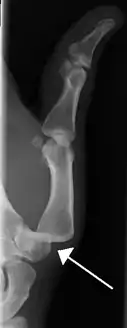

Radiograph of right fifth phalanx bone dislocation

Radiograph of right fifth phalanx dislocation resulting from bicycle accident

Right fifth phalanx dislocation resulting from bicycle accident